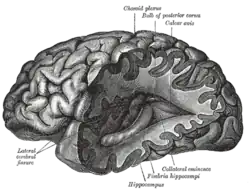

| Human brain | |

|---|---|